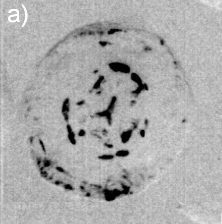

As summarized in Fig. 2, the image contrast criterions of DEI allows characterization of the scattering properties of the observed internal structures in the lenses. Diffuse-scattering, refraction, and absorption images were collected respectively at the tail (T), shoulder (S), and center (C) of the analyzer window, some good examples are shown in Fig. 3. In the former type of image, the amounts of diffuse-scattering around the internal structures are consistent to the type of scattering expected for an aggregation of tiny precipitates without a well defined boundary, as in Figs. 3(a) and 3(c). On the other hand, refraction images have shown aggregations with dense cores, Fig. 1(d) and 3(d), capable to refract X-rays in an opposite sense of air bubbles, arrow in Fig. 3(f). It indicates that the precipitates are denser than the lens tissue.

By recording the transmitted beam image before the analyzer, as in conventional absorption radiography, the X-ray attenuation through aggregates with dense cores provide visible contrast in some cases. A few millimeters in length observed in frontal view, e.g. Fig. 3(a), provide a lateral attenuation in side view, Fig. 3(b), that is comparable to the attenuation of bones. Although elemental analysis is necessary to assure the composition of the precipitates, they probably are rich in calcium.

Dilute concentrations of precipitates without cores have also been observed, Figs. 3(e) and 3(f), as well as clinical cases of cataract with well-defined Y-sutures but with no distinct amounts of precipitates. In these cases, which correspond to 60% of the analyzed cases, there are significant scattering at the suture marks that can be generated either by local compaction of fiber cells or accumulation of precipitates along the marks, as for instance in Figs. 3(g) through 3(l). Refraction images show the extension of compaction areas while diffuse-scattering images can revel the presence or not of precipitates at the sutures. Absorption images (center of the analyzer window) provide essentially the same information of diffuse-scattering ones.